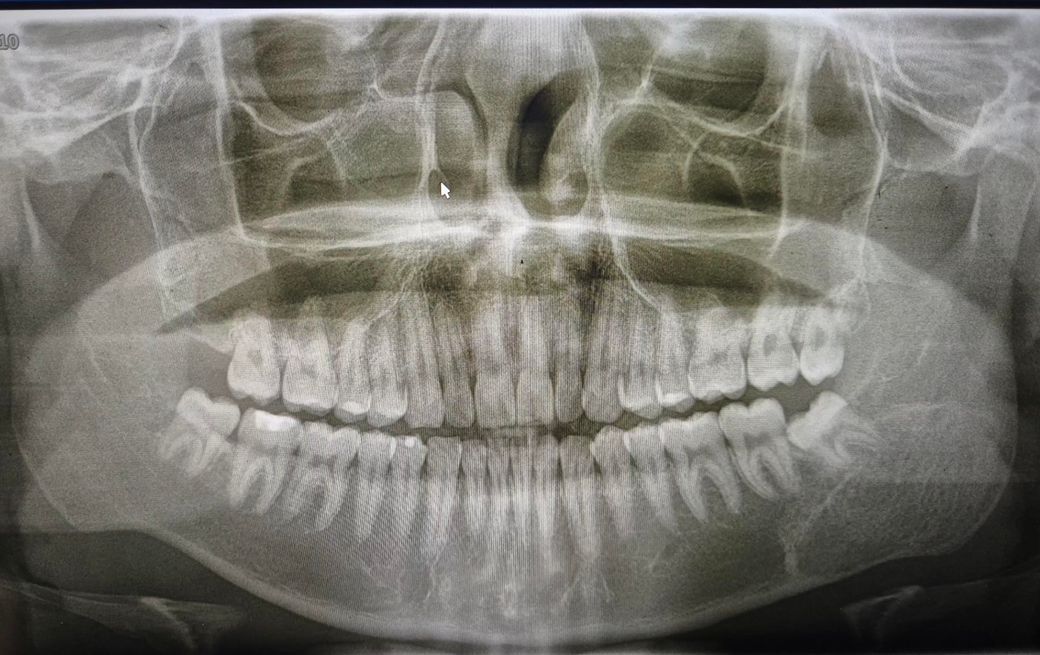

좌측 턱에 뭔가 있어서 질문드립니다.

치과에서 사랑니 빼다가 발견 한건데 저게 뭘까요?

뭔가 딱딱해 보인다고 들었던거 같은데, 콧구멍 쪽에도 있는거 같다는데 골종양 이런건가요?

• 1번 째 사진

엑스레이 상으로 크게 문제가 있어 보이는건 없습니다. 그냥 경화가 된부분이 보이는거 같습니다.

골육종 등 악성종양의 양상은 아닌 것으로 보입니다. 엑스레이 양상으론 fibrous dysplasia의 가능성이 있어보이나 정확한 진단은 대학병원 영상의학과 가보셔야 합니다.